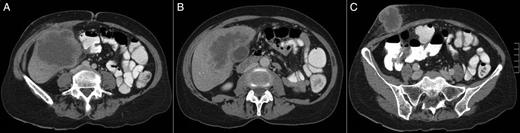

(A–C) A CT scan revealing a large hepatic mass invading the abdominal wall.

Cutaneous metastasis (CM) is an uncommon manifestation of visceral malignancies. Adenosquamous carcinoma of the gallbladder is a rare variation in gallbladder carcinoma (GBC), associated with worse prognosis. We present the case of a 56-year-old woman who presented with an inflamed lump on her abdominal wall. Computed tomography (CT) revealed a large mass from the gallbladder invading the abdominal wall. She underwent liver resection with regional lymphadenectomy. Pathology analysis revealed a 12-cm pT3N0 GBC. Hospital discharge occurred at post-operative Day 20. She recurred and died 10 months after surgery. Survival after the diagnosis of CM is dismal. The present case was a diagnostic trap. First, the patient's skin lesion presented as a cutaneous abscess and biopsy revealed a squamous cell cancer. A CT scan suggested a continuous mass involving the abdominal wall. CM was only suspected during surgery when no continuity between the tumour and the abdominal wall was identified.

The present case was a diagnostic trap. First, the patient's skin lesion presented as a cutaneous abscess and was treated as such, and then the skin biopsy revealed a squamous cell cancer. Clinical examination and CT scan suggested a continuous mass involving the abdominal wall and liver. CM was only suspected during surgery when no continuity between the liver tumour and the abdominal wall was identified. It is interestingly to note that recurrence first occurred at skin and adrenals, which can be probably explained by the ectodermal origin of the medullary area.